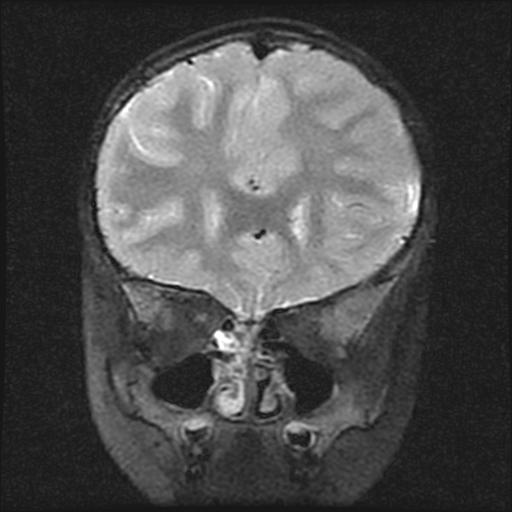

6岁小儿,左侧视神经瘤术后。现左侧视力减退。